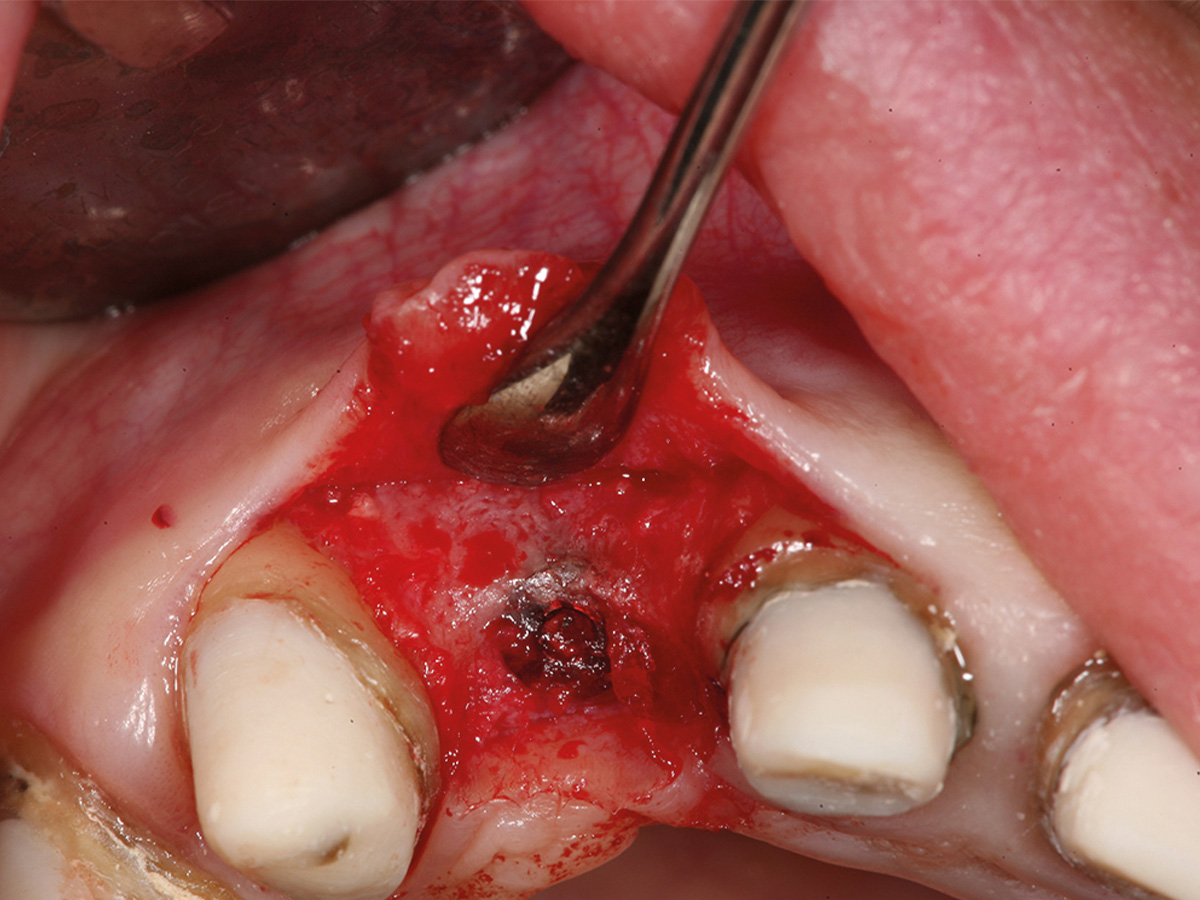

Abbildung 4

Intraoperative Situation mit koronaler Knochenbrücke und extraalveolär imponierendem Implantat (Biomet 3,2 x 13).